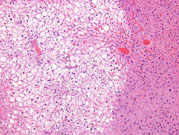

This is an example of focal fatty change with affected hepatocytes containing a mixture of macrovesicular and microvesicular fat.

A specific example of focal fatty change seen in mice and present in the median lobe represents tension lipidosis when it is near the falciform ligament and gallbladder.